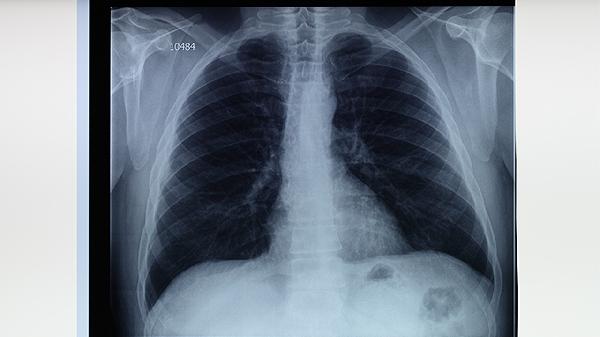

肺結(jié)核會通過什么途徑傳染?

肺結(jié)核主要通過空氣傳播,患者咳嗽、打噴嚏或說話時,會將含有結(jié)核桿菌的飛沫釋放到空氣中,健康人吸入這些飛沫可能被感染。預(yù)防肺結(jié)核的關(guān)鍵是避免與患者密切接觸、保持良好通風、接種卡介苗。

1.空氣傳播是肺結(jié)核最主要的傳染途徑。當肺結(jié)核患者咳嗽、打噴嚏或大聲說話時,會將含有結(jié)核桿菌的飛沫釋放到空氣中。這些飛沫在空氣中懸浮,健康人吸入后可能感染結(jié)核桿菌。飛沫傳播的范圍通常在1-2米內(nèi),但在密閉空間內(nèi)傳播風險更高。